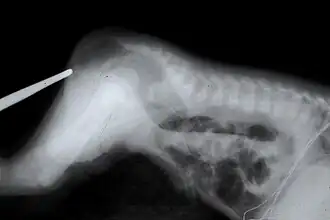

Radio montrant une imperforation de l'anus